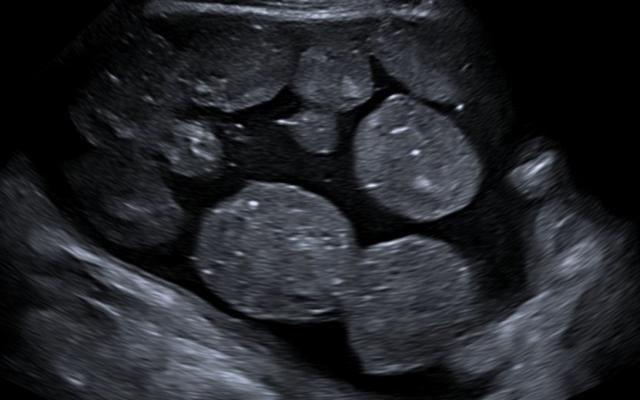

Echo van een cyste.

Een 34-jarige vrouw kwam bij de huisarts vanwege misselijkheid en diarree. De klachten waren ontstaan 3 uur nadat zij sushi had gegeten. Haar gewicht en buikomvang waren de afgelopen maanden niet toegenomen en de menstruatiecyclus was regelmatig. Bij lichamelijk onderzoek was een zwelling in de onderbuik voelbaar die craniaal reikte tot halverwege de afstand tussen de symphysis pubica en de navel. De zwangerschapstest was negatief. Echografisch onderzoek in de eerste lijn liet een grote cyste in de onderbuik zien. Daarop werd de patiënte naar ons verwezen. Wij dachten aan een ovariumcyste. Bij echografie zagen wij op de plaats van…